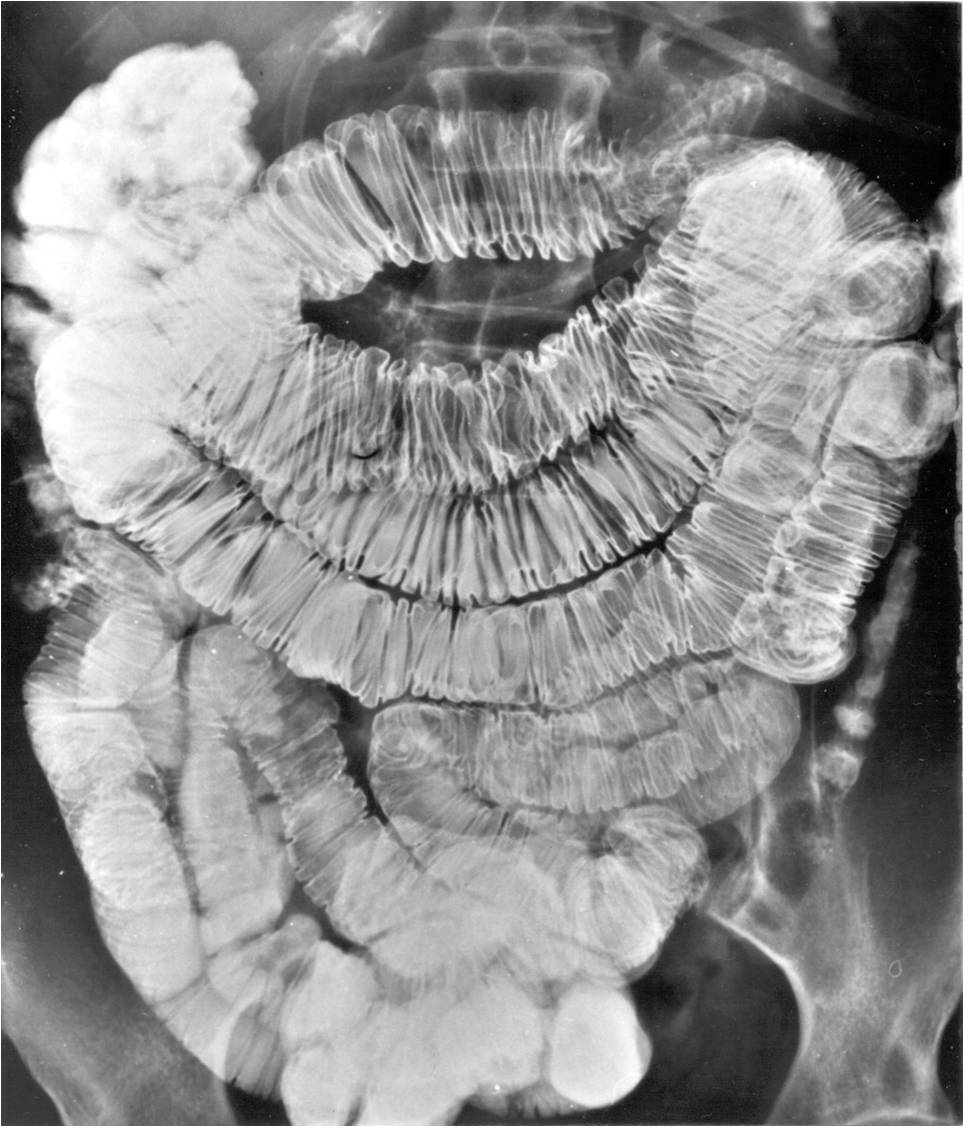

Image

Fig.21.: Radiograph of selective enterocylsis

Fig.20.: Follow-through examination

On the abdominal radiograph distension of the small bowel loops and air-fluid levels can be identified. It is important to describe forwarding of the contrast media by time or if mechanical obstruction is seen. Morphology of the intestinal loops could not be assessed with this method. This study is specifically conducted to examine the transit function only.